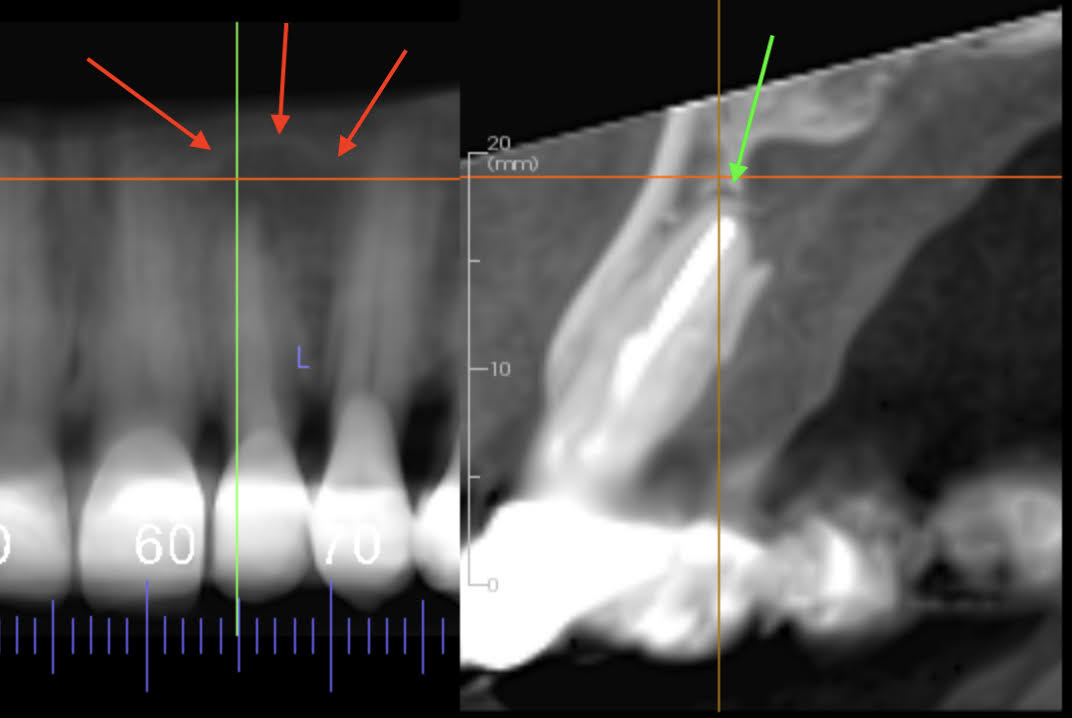

Two images, pre-extraction UL2. The left is a reconstructed cropped panoramic CBCT providing an image similar to a periapical intraoral radiograph. The red arrows show the outline of a well defined corticated unilocular apical radiolucency of UL2 ( 3 red arrows). However, the Right image is a cropped reconstructed sectional alveolar arch which shows UL2 apex has a 0.5 to 1.0 mm radiolucency (green arrow). The image also shows that the lamina dura is intact and NOT part of the large palatal concavity superior to the apex. The radiolucency is very small and probably from fibrous healing of apex but may also be granulation tissue from chronic apical periodontitis. At this stage with no symptoms the correct management would be to monitor this 6 months later with a periapical radiograph to see if there is any radiographic change.